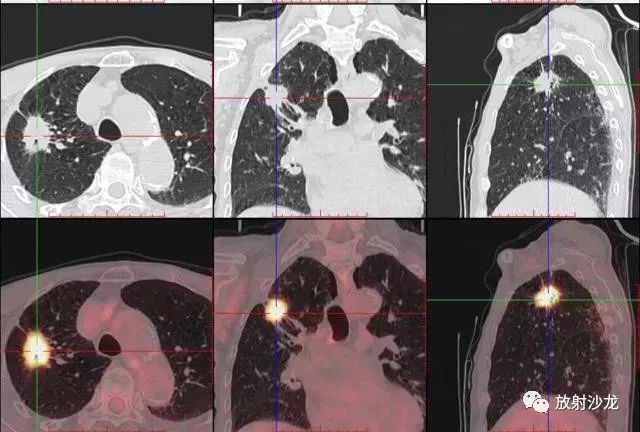

PET-CT等于PET+CT,包含PET(功能分子影像)與CT(解剖影像)的最優(yōu)化組合;即同時(shí)具有PET和CT的功能,但它絕不是二者功能的簡(jiǎn)單疊加,因?yàn)镻ET與CT優(yōu)勢(shì)互補(bǔ),“1+1>2”。PET-CT除了具備PET和CT各自的功能外,其獨(dú)有的融合圖像,將PET圖像與CT圖像融合, 可以同時(shí)反映病灶的代謝,可以早期診斷疾病的同時(shí),明顯提高診斷的準(zhǔn)確性。

18F-FDG(氟脫氧葡萄糖)是葡萄糖的類(lèi)似物,是臨床最常用的顯像劑;18F-FDG能反映體內(nèi)葡萄糖利用狀況。腫瘤細(xì)胞內(nèi)可積聚大量18F-FDG,但是18F-FDG僅僅是葡萄糖類(lèi)似物,腫瘤細(xì)胞攝取后不能進(jìn)一步代謝,屬于“只進(jìn)不拉”,能在腫瘤細(xì)胞內(nèi)積聚,經(jīng)PET-CT顯像可顯示腫瘤的部位、形態(tài)、大小、數(shù)量及腫瘤內(nèi)的放射性分布。同時(shí)腫瘤細(xì)胞的原發(fā)灶和轉(zhuǎn)移灶具有相似的代謝特性,一次注射18F-FDG就能方便地進(jìn)行全身顯像,18F-FDG PET-CT全身顯像對(duì)于了解腫瘤的全身累及范圍具有獨(dú)特價(jià)值。